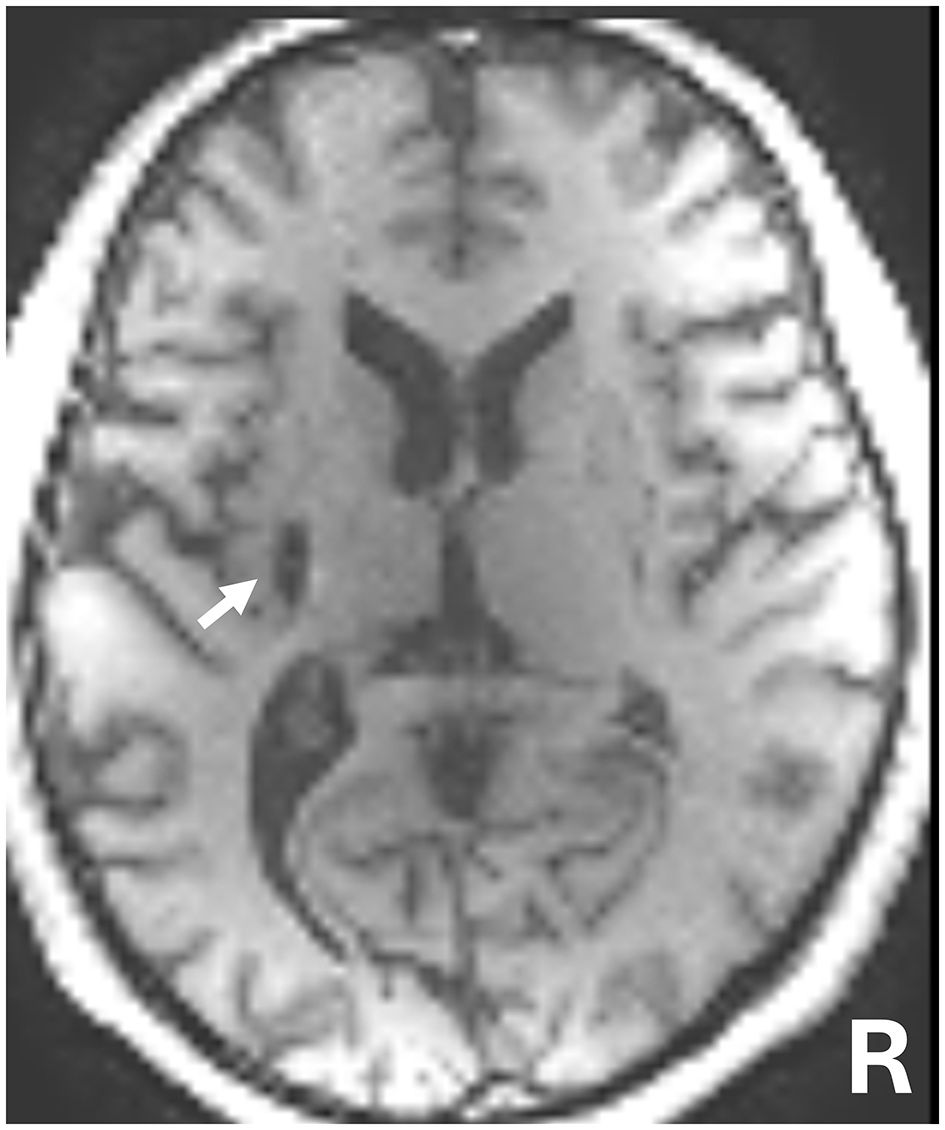

The patient was a 50-year-old man with chronic right hemiparesis following a left putaminal hemorrhage 5 years prior (Figure 1). The patient initially underwent 5 months of intensive inpatient rehabilitation following stroke onset. Four years post-stroke, he also participated in outpatient physical therapy sessions (once to three times per month), which included task-oriented training. However, no marked improvements in upper-limb function were observed, and these sessions were discontinued 8 months before the start of this study. Since then, the patient has not received any rehabilitation interventions. When the patient began outpatient physical therapy 1 year prior to this study, his shoulder flexion was limited to 150° and abduction to 120°, with no other noted range of joint motion restrictions.

Figure 1. T1-weighted magnetic resonance imaging (MRI) 5 years following brain hemorrhage onset. The white arrow indicates the left putamen lesion.